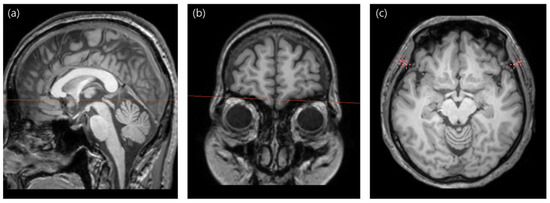

2.3. TMT Measurement